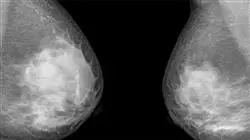

2.1. Exame clínico e instrumental em patologias mamárias

2.1.1. Diferentes métodos exploratórios

2.1.2. Tipos de métodos de diagnóstico

2.3. Cancro da mama

2.3.1. Epidemiologia e fatores de risco

2.3.2. Prevenção primária. Diagnóstico precoce. Lesões não palpáveis